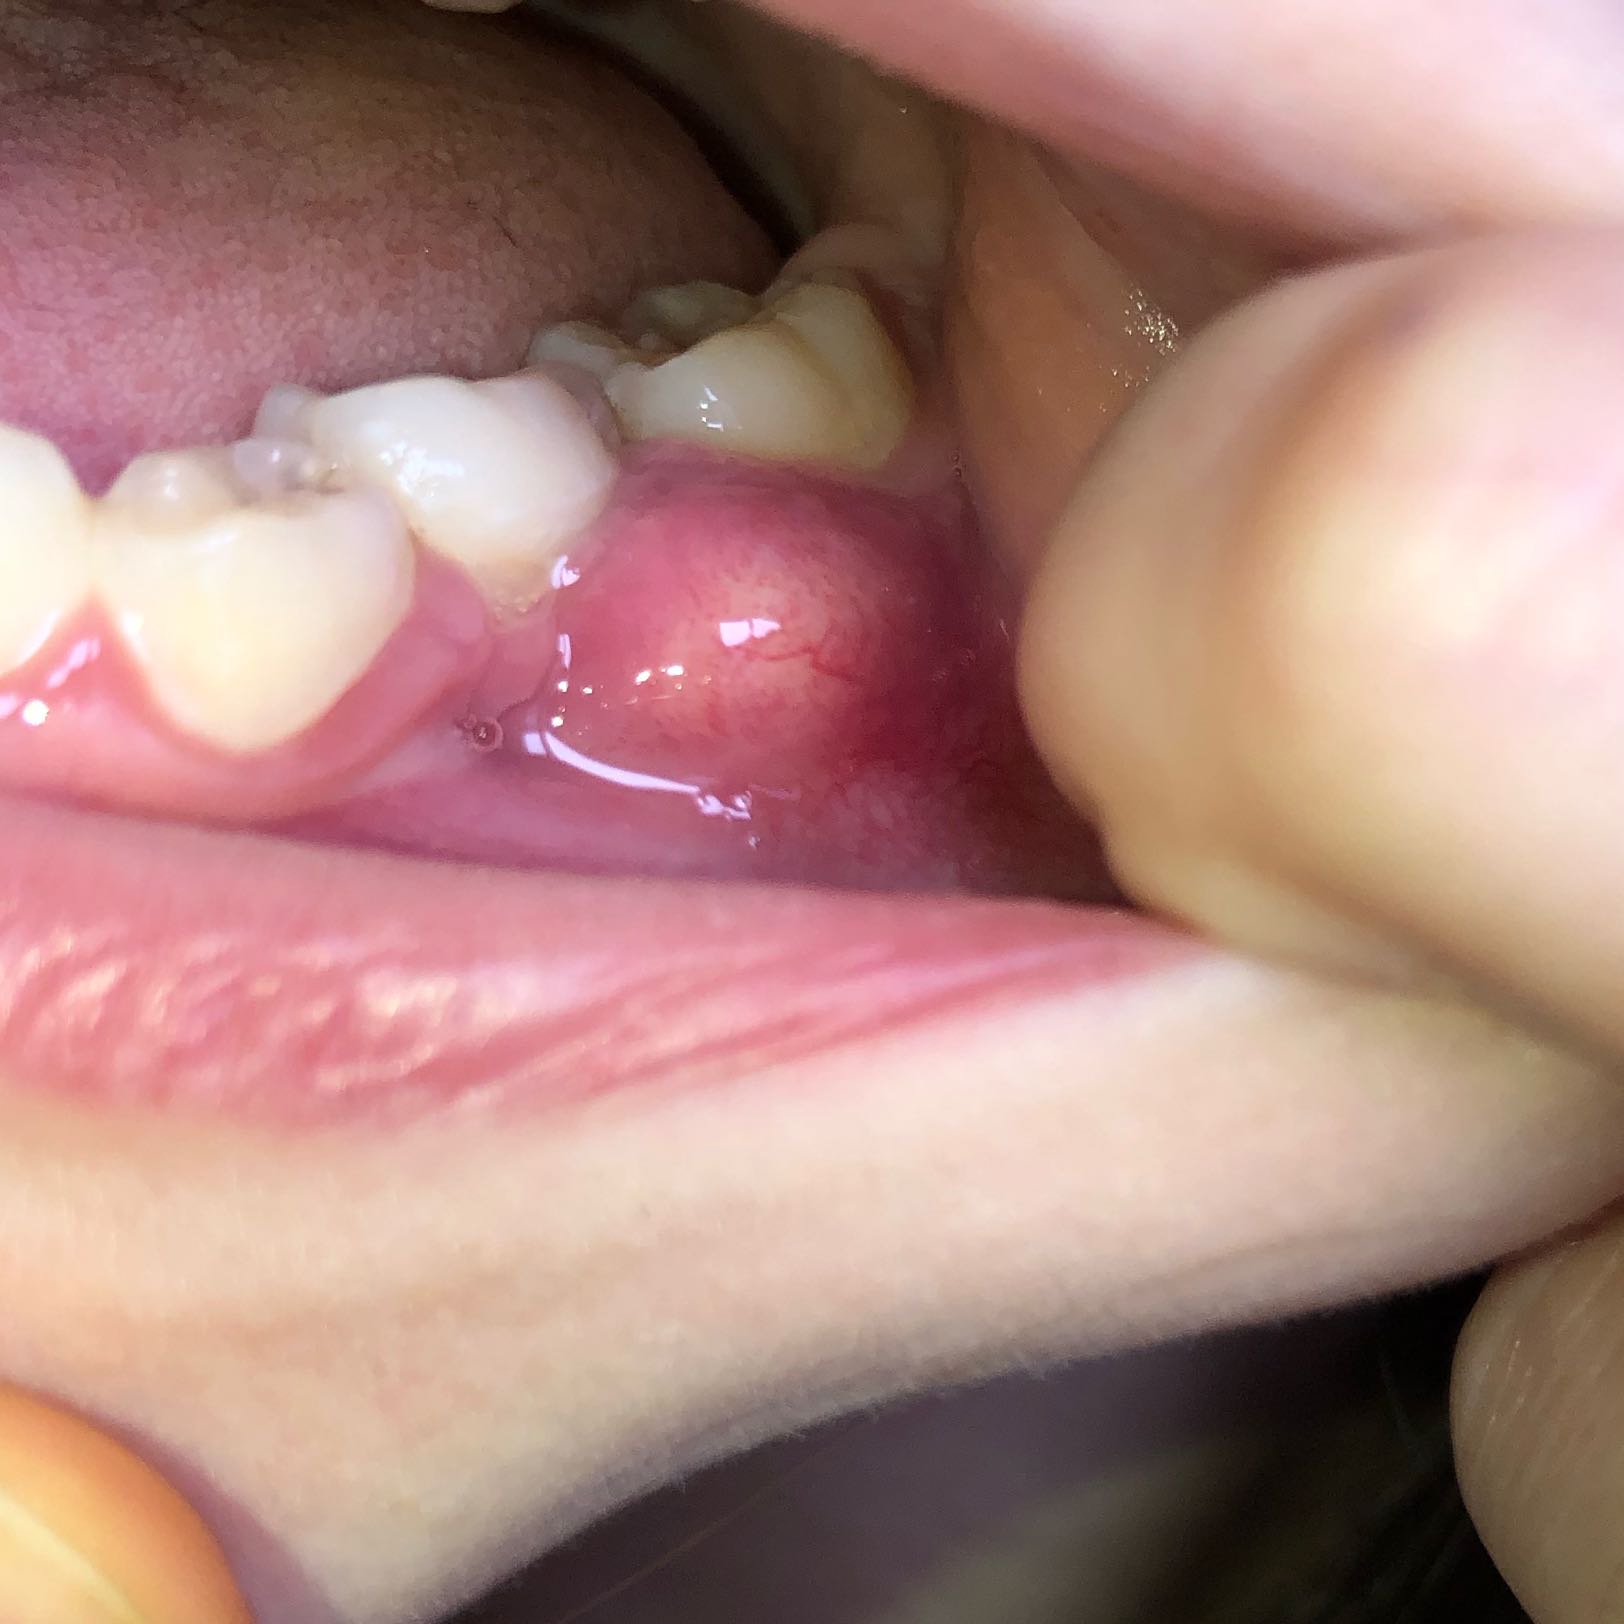

Beule am zahnfleisch ohne schmerzen. Die braucht sie dann auch. In diesen Fällen sollte man am besten zwei bis drei Tage abwarten und schauen ob sich die Situation bessert. Das sieht nach einer stark entzündeten Zahnfleischtasche aus.

Am Zahn und Zahnfleisch können viele Probleme entstehen. Die beuele ist vermutlich ein sich ausbildender abszeß der von alleine nicht besser wird auch die schmerzen werden nicht besser. Der wird die Stelle behandeln und ihr wahrscheinlich Antibiotika verschreiben.

Weitere Auslöser können sein. Eine Eiterbeuleentsteht durch die Entzündung im Knochen und am Zahn. Probleme am Zahn wie Zyste Fistel Eiter Schwellung.

Entweder wurde das Zahnfleisch durch mechanische Reize verletzt oder eine Infektion mit Viren Bakterien oder Pilzen ist schuld an der Entzündung. Die Beule ist unnachgiebig aber sie ist ja noch ein Kind. Diese Bakterien können einen Abszess verursachen selbst wenn die Zähne gesund und frei von Löchern sind.

Mit der richtigen Betäubung ist die Behandlung vom Zahn ohne Schmerzen. Eine Schwellung des Zahnfleisches ist ein Anzeichen für eine Entzündung.

Es entsteht ein sogenannter Abszess. Sie sollten jedoch sofort Ihren Arzt anrufen wenn Sie zusätzlich zu einer Beule eines der folgenden Symptome bemerken. Werde auf jeden Fall zum Zahnarzt müssen habe aber eine riesen Angst das sich nun eine Wurzelentzündung oder sogar noch schlimmeres dahinter verbergen könnte. Damit muss sie DRINGEND zum Zahnarzt. Das kann an einer leichten Entzündung oder einer Wucherung liegen. Zudem ist das frühe Stadium einer Infektion des Zahnfleisches meist schmerzlos. Ist ein Zahn oder ein Zahnnerv entzündet schmerzt nicht nur der Zahn selbst. Die braucht sie dann auch. Fragt am besten den Ärztlichen Bereitschaftsdienst Tel.

Sie sollten jedoch sofort Ihren Arzt anrufen wenn Sie zusätzlich zu einer Beule eines der folgenden Symptome bemerken. Mit großer wahrscheinlichkeit ist der zahn abgestorben kann auch symptomolos passieren. Deshalb empfindet der Betroffene keine Schmerzen obwohl sich die Entzündung mit großer Wahrscheinlichkeit schon tief in den Kiefer hinein vorgearbeitet hat. Fragt am besten den Ärztlichen Bereitschaftsdienst Tel. 116 117 wer heute Zahnärztliche Bereitschaft macht. Damit muss sie DRINGEND zum Zahnarzt. Weitere Auslöser können sein.